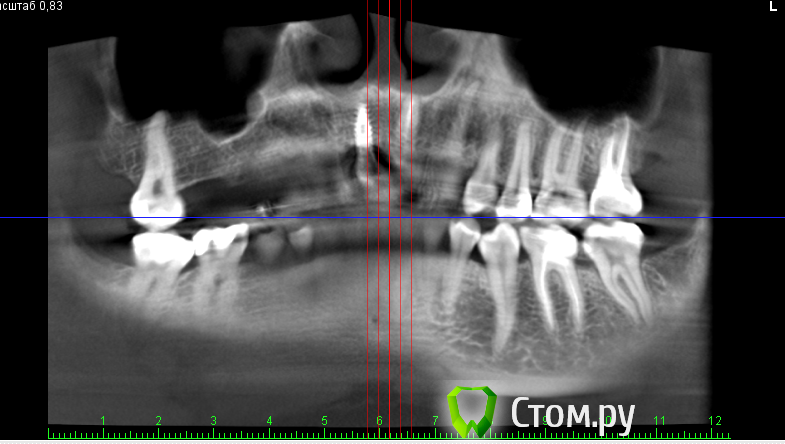

***Irene*** Опубликовано 22 октября, 2014 Поделиться Опубликовано 22 октября, 2014 (изменено) Уважаемые знатоки!Сделали КТ верхней челюсти с имплантом, потому что коронку ну никак не вместить по человечески, десна ходуном ходит, и увидели такую картину (см картинки). То, что имплант стоит слишком глубоко в нёбо и не в зубном ряду - видно даже невооруженным и непрофессиональным взглядом, шейка коронки, как видно на снимке, под большим углом, но коронка все равно торчит вперед.В общем, вердикт доктора - удалять и ставить новый с предварительной аугментацией. Сразу скажу, что в клинике, в которой ставили, клялись, что это нормально, но я оттуда сбежала, вердикт уже из новой клиники.Вопросы:1) На самом ли деле имплант стоит в кости криво?2) Не опасно ли удаление прижившегося импланта и какие могут быть последствия?3) Какова последовательность в данном случае: удаление+аугментация, затем новая имплантация через полгода, затем коронка через полгода? Изменено 22 октября, 2014 пользователем ***Irene*** Ссылка на комментарий

anvladd Опубликовано 23 октября, 2014 Поделиться Опубликовано 23 октября, 2014 (изменено) на 3 кт видно что он косо стоит. Изменено 23 октября, 2014 пользователем anvladd Ссылка на комментарий

***Irene*** Опубликовано 23 октября, 2014 Автор Поделиться Опубликовано 23 октября, 2014 Ну, в общем-то, внутри рта это выглядит именно так, как на 3 КТ - смещение из зубного ряда, причем, нормальное такое. Врач говорит, что это из-за того, что на КТ 4 недостаток кости с внешней стороны и что процесс будет усугубляться, поэтому нужно нарастить кость, удалив этот имплант, и вставить новый. Фиг с ней, с кривизной, больше волнует вопрос, на самом ли деле там спереди не хватает кости и она может "уйти" окончательно, из-за чего имплант вывалится сам? И не развезет ли мне всю челюсть удалением импланта (ведь он же врос в кость), что потом всякие косметические операции понадобятся и пр. Ссылка на комментарий